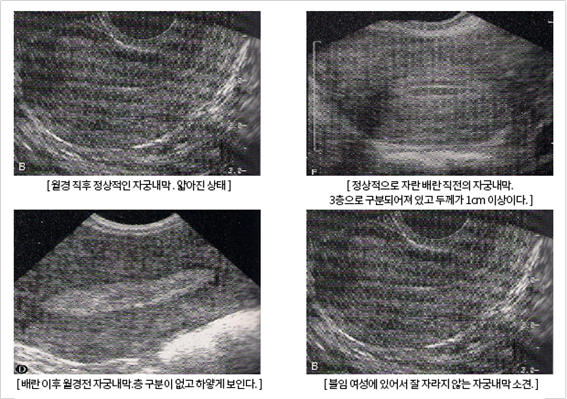

������ ���¸� �ڼ��ϰ� Ȯ���� �� �ֽ��ϴ�. ��ħ���� ������� �����ĸ� ����� ��ó���� ���� �ڱ� ������ ���¸� �����ϰ� �����ķ� ������ ���� �־��, �ڱó��ð��� ���ؼ� �ڼ��ϰ� �ڱó����� ���¸� �� ���� �־��.

�ջ���� �ڱó��� ���°� �����ǰ� �ֽ��ϴ�.